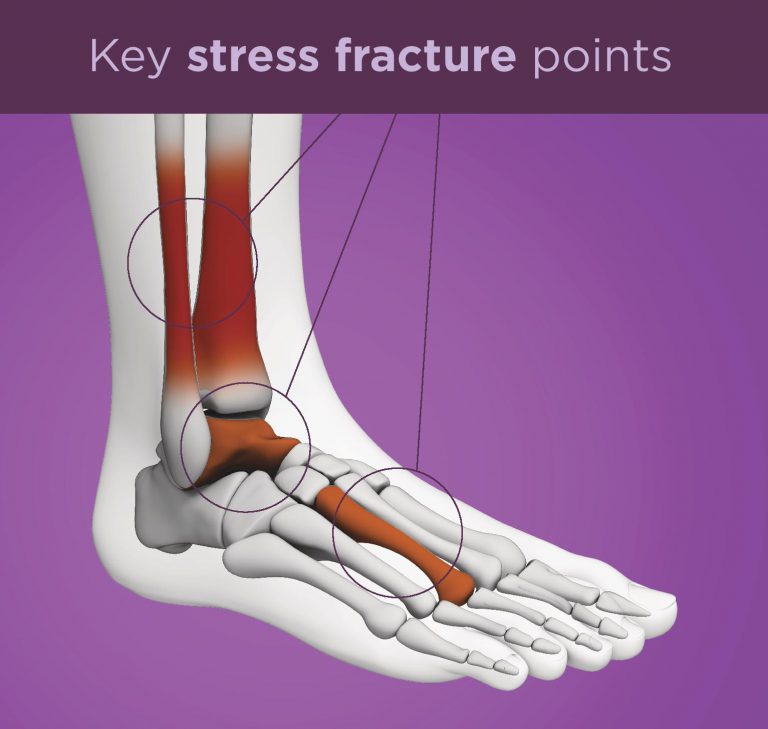

Shin splints and stress fractures often get categorized as the same thing, panchal said, explaining that the main differences are that, while shin splints are caused by. Stress fracture should be suspected in persons with a drastic recent increase in physical activity or repeated excessive activity with limited rest. Mri is the most sensitive modality for detecting stress fracture, and may also be useful for differentiating ligamentous/cartilaginous injury from a bony injury.

36, 51 scintigraphy is able. Most stress fractures are caused by. One or more of the following diagnostic imaging exams may be used to confirm the presence of a foot stress fracture.